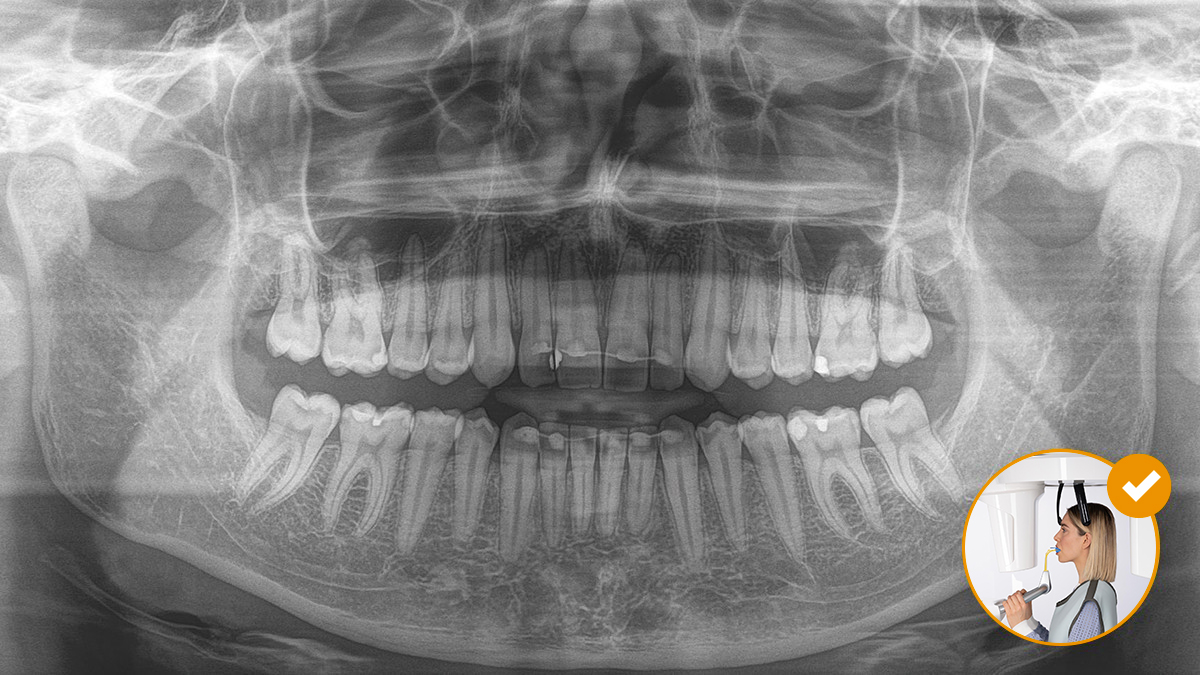

Relaxed and pleasant procedures are equally important for everyone, the patients and the staff alike. It is satisfying and motivating when everything goes according to plan and things go smoothly. The use of Orthophos or Axeos with Sidexis 4 provides you with targeted support. The X-ray systems are simple to use, yet unique in their diagnosis possibilities.. This ensures that every aspect of the treatment process creates a positive experience.

Correct patient positioning leads to high image quality to support an accurate diagnosis and facilitates and improves patient experience.

This is our 10-point concept for easy patient positioning and X-ray imaging. It is primarily about two things: high image quality and comfort for the patient and the assistant.